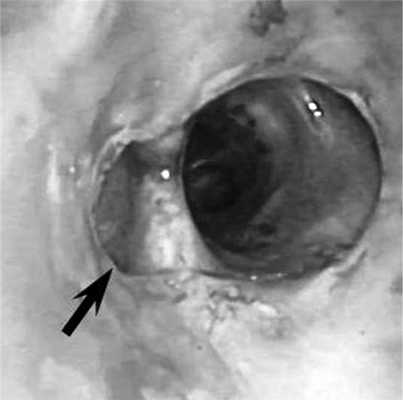

Рис. 4. Состояние после стентирования промежуточного бронха. В просвете промежуточного бронха определяется самофиксирующийся стент ЭПТС 9 ×15. Произведено моделирование стента для обеспечения адекватной вентиляции средней доли и 6-го сегмента нижней доли правого легкого (указано стрелкой).